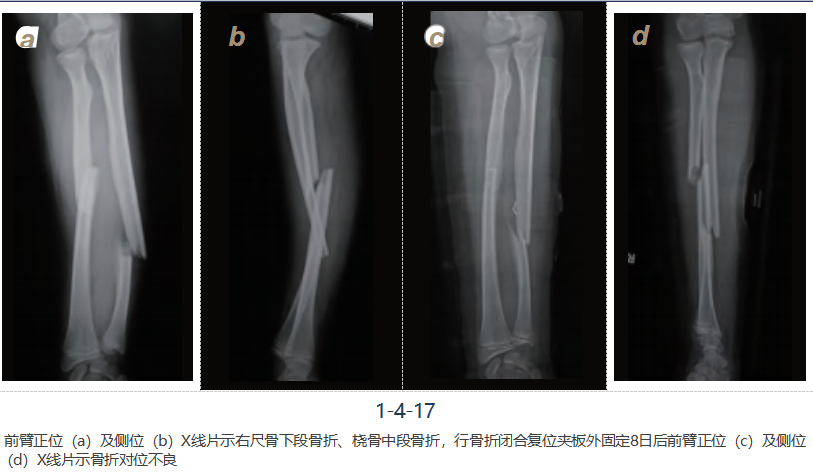

病例三

男,12岁,摔伤致右前臂肿胀、压痛、畸形、活动受限,诊断为右尺桡骨骨折,行右尺 桡骨骨折闭合复位弹性钉内固定术,术后恢复良好(图1-4-17~19)。